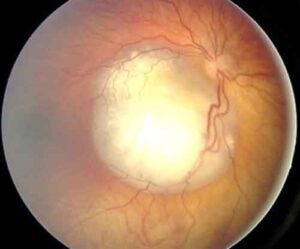

Sta dando risultati positivi il protocollo messo in atto dall'azienda ospedaliera delle Scotte di Siena per la cura del retinoblastoma,...

Raro ma aggressivo, questo tumore colpisce soprattutto i bambini Si guarisce quasi sempre e ora si punta a preservare la...